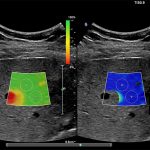

Imagini clinice:

Aplicatii: